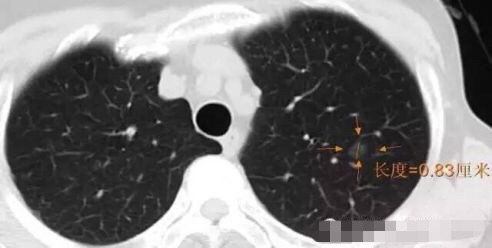

随访3年,GGO直径基本没有变化

2013年12月

2014年7月

2015年5月

2016年10月